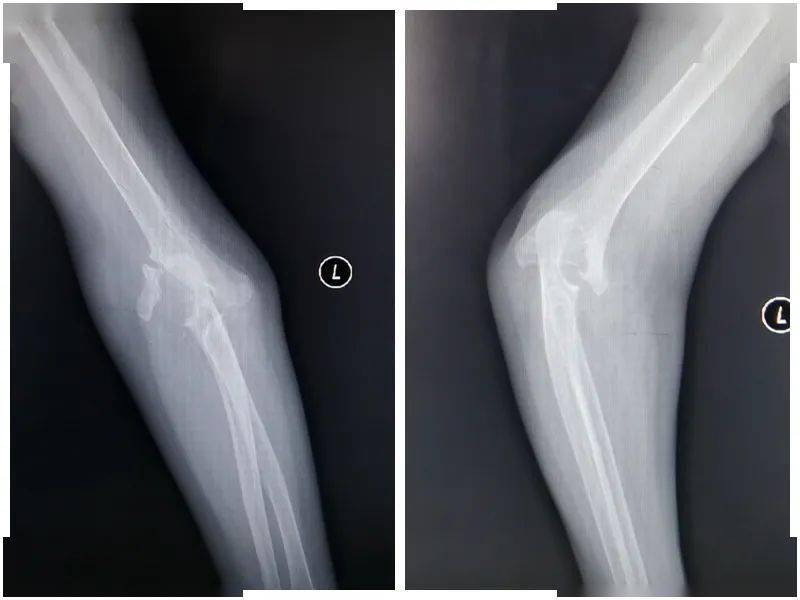

78岁女性,重度骨质疏松,尺桡骨远端开放,粉碎性骨折.治疗前正侧位片

图片尺寸1080x1440